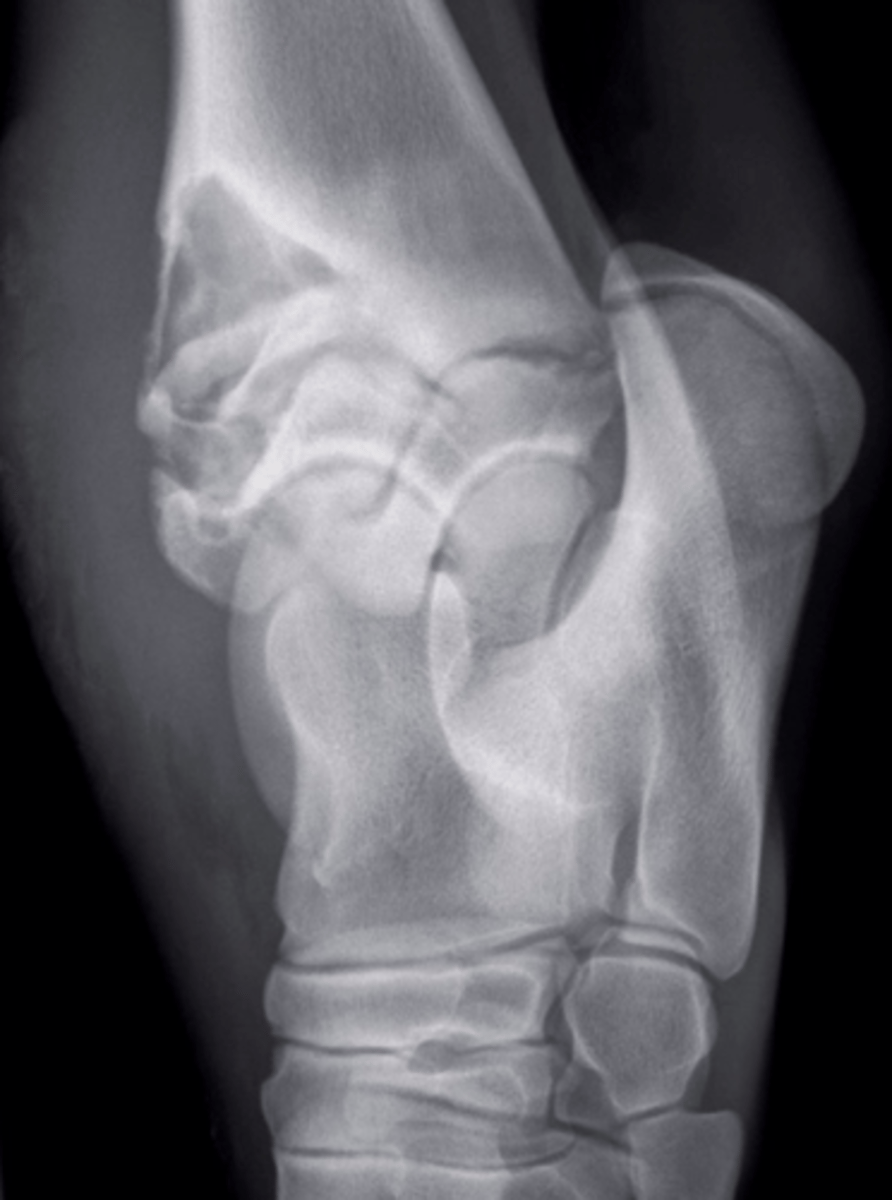

Physeal

Identify the type of infection?